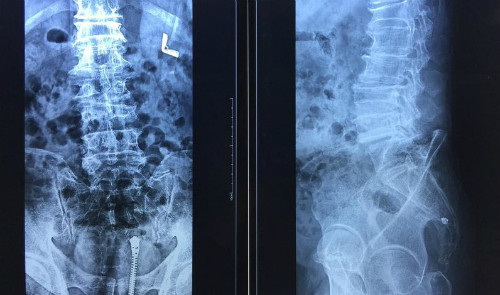

| Cột sống lưng của bệnh nhân bị biến dạng. |

Các bác sĩ khoa Chấn thương chỉnh hình cho biết, ông cụ bị loãng xương, tiểu đường, xơ vữa động mạch, cột sống biến dạng rất nhiều. Hậu quả của việc đắp thuốc của thầy lang là màng cứng tủy dính vào dây chằng vàng và các thành phần xung quanh.